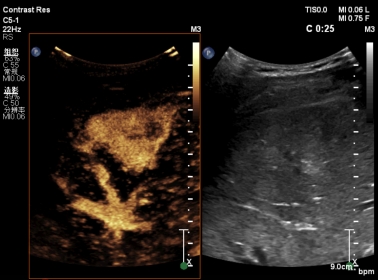

超声造影技术是一项无创影像学检查技术,比普通超声及彩色多普勒超声能提供更丰富、更明确的诊断信息,且快速简便,可重复操作性非常好,临床实用性很高,尤其使肝脏肿瘤的诊断符合率明显提高,超过90%,可以与增强CT、MRI相媲美。

肝脏肿瘤超声造影技术,显示肿瘤内微血管灌注情况